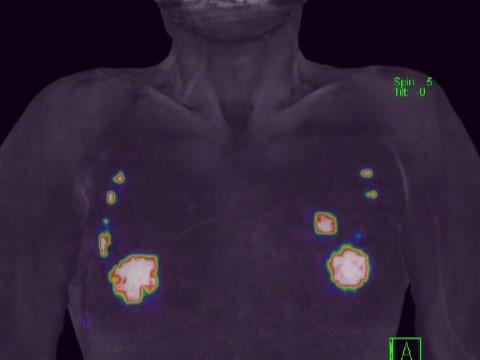

腫瘍領域ではFDG-PET/CTを駆使して、がんの原発、転移、再発診断を行っています。